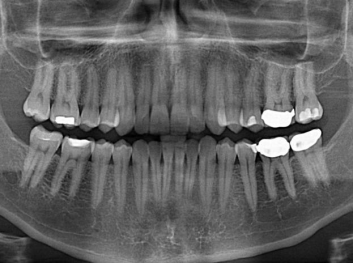

Adam Celiz,是來自諾丁漢大學的研究人員,他和同事開發(fā)的這種新型合成生物材料,能刺激干細胞在牙髓部的生長。與普通材料一樣,這種合成材料被填充到牙齒并用UV光硬化。

在體外測試中,材料刺激干細胞進入牙本質(zhì)的增殖和分化速度,促進形成牙齒骨組織。研究人員認為,一旦材料在受損牙齒中應用,這些干細胞可以自動修復來自填充物上的損壞。在本質(zhì)上,該生物材料將使牙齒自愈。